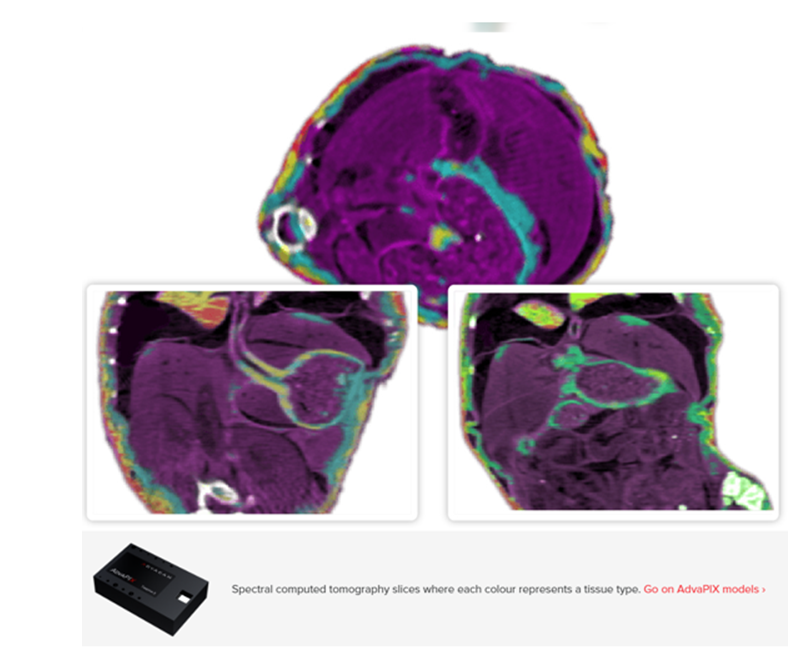

SIDILAB presenta una seríe de nuevos sensores desarrollados por ADVACAM para aplicaciones biomedicas RADIOGRAFÍA ESPECTRAL Los detectores de recuento de fotones destacan en bioimagen por su alta sensibilidad y rango dinámico. La alta sensibilidad de los detectores de recuento de fotones los hace útiles en la obtención de imágenes de objetos con baja atenuación de los rayos X. Objetos ligeros, como los tejidos. Por ello, estos detectores son ideales para aplicaciones relacionadas con la biología. El alto rango dinámico revela características en las muestras que permanecen ocultas para otros tipos de detectores de imágenes de rayos X. Además, la estructura del modelo puede visualizarse gracias a la sensibilidad espectral del dispositivo. Sólo se pueden resaltar estructuras específicas y suprimir otras ![]() TOMOGRAFÍA COMPUTARIZADA ESPECTRAL La tomografía computarizada espectral mejora la obtención de imágenes en 3D, lo que permite avanzar en la identificación de tejidos y la investigación sobre el tratamiento del cáncer. La radiografía espectral puede ampliarse a 3D mediante tomografía computarizada. Esto permite reconocer distintos tipos de tejido en su forma natural. Este nivel de información puede ser beneficioso para la investigación del tratamiento del cáncer, ya que proporciona mejores datos para la planificación de la irradiación. ![]() DIFERENCIACIÓN DE TEJIDOS BLANDOS Nuestras innovadoras cámaras de imagen emplean tecnología avanzada para mejorar la claridad y el detalle en el análisis de muestras extensas de tejido. Nuestros dispositivos emplean una combinación única de imágenes de absorción y mejora del contraste de fases, lo que permite una visualización clara de detalles específicos en muestras de tejido de gran tamaño. Hemos demostrado la potencia de esta tecnología obteniendo imágenes de una muestra de pulmón de ratón desinflado. Las técnicas de imagen tradicionales tenían dificultades para diferenciar entre la estructura granular de los alvéolos y otras estructuras pulmonares. Nuestro avanzado sistema, sin embargo, puede distinguir entre alvéolos y distintos tipos y estructuras de tejido. Nuestro sistema de rayos X de alto contraste ajusta con precisión el espectro del haz de rayos X y los niveles de sensibilidad energética del detector para generar imágenes detalladas. Esta tecnología es una potente herramienta para el análisis de tejidos, ya que revela características normalmente ocultas debido al bajo contraste, revolucionando así el estudio de las microestructuras pulmonares. ![]() ![]() Este vídeo muestra una grabación a cámara lenta de los latidos del corazón de un ratón. El corazón del roedor late a una frecuencia de 670 latidos por minuto, diez veces más rápido que un corazón humano. La grabación se realizó con nuestro detector AdvaPIX a una velocidad de 1.000 fotogramas por segundo. El tejido óseo se suprimió mediante postprocesado para que el corazón fuera visible incluso detrás de la caja torácica. En el vídeo puede observarse cómo se oscurecen o aclaran las distintas cavidades y aurículas del corazón, lo que corresponde al movimiento real de la sangre en el interior del órgano. En este caso, no se utilizó ningún agente de contraste. Ir a los modelos AdvaPIX ' ADVACAM es una empresa Fundada en 2013, Su revolucionaria tecnología surgió de la investigación como parte de la colaboración científica original para la física de altas energías iniciada en la década de 1990 en el CERN, y sIguen siendo parte integrante del equipo de Medipix que desarrolla las tecnologías de imagen del futuro. La innovación es su motor de crecimiento y trabajan sin descanso para ampliar los límites de lo posible con sus soluciones de imagen. Los detectores patentados de ADVACAM se encuentran entre las tecnologías de imagen más avanzadas del mundo. Más información aquí En caso de que sea de su interés, será un placer que tengamos una reunión presencial/online. sidilab@sidilab.com |